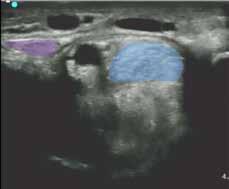

Figure 4. Images of the carpal canal ultrasound were obtained from simultaneous video of probe position and ultrasound feed. The photos on the left (A) were the same time stamp as the images (B) and (C) for each row. (B) and (C) are the same image; (b) is enhanced with color for clarity and (C) is labeled. The level indicated on each row corresponds to the arrows on the anatomical dissection in Figure 3.

Legend: SDF - superficial digital flexor tendon, DDF - deep digital flexor tendon, SCL - superior check ligament (AL-SDFT), FCR - flexor carpi radialis, RAD - radius, ACB - accessory carpal bone.

Figure 3. The arrows depict the approximate level of the ultrasound probe in the reference images below. Level 1 - SDF in the distal carpal canal Level 2 - Insertion of SCL into SDF Level 3 - Mid SCL Level 4 - Near origin of SCL .